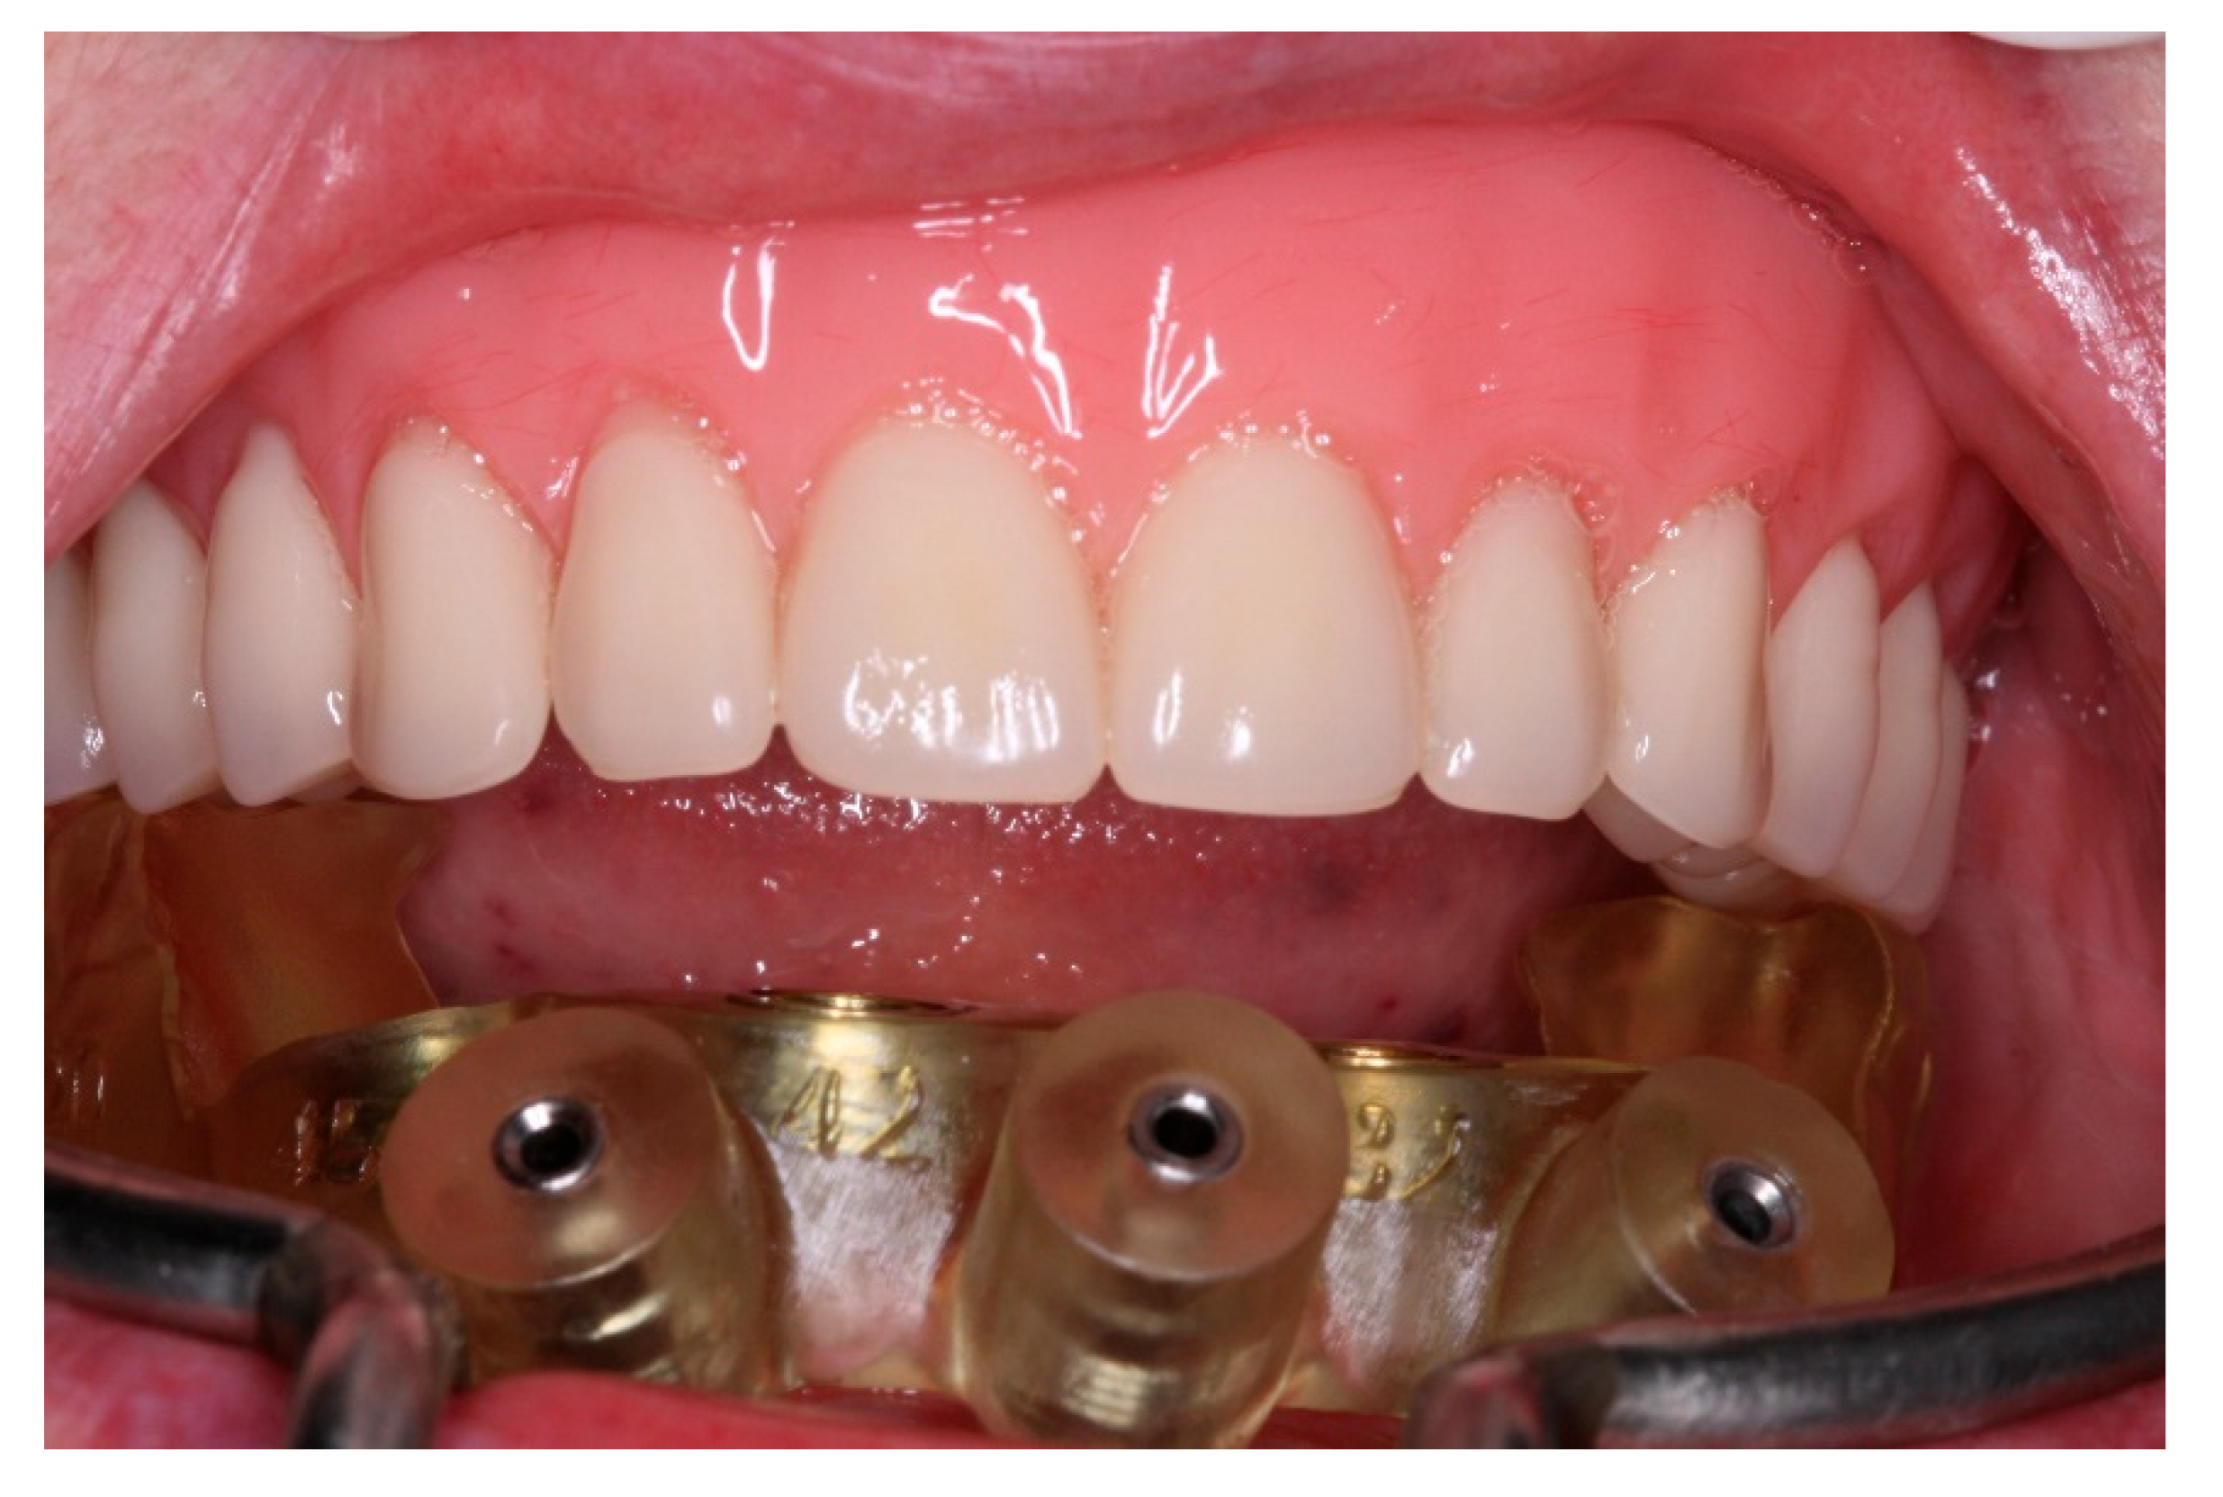

Figure 20. Lingual view of the new fixed screw-retained full-arch rehabilitation.

Figure 21. Buccal view of the new fixed screw-retained full-arch rehabilitation in occlusion.

After a healing period of 3 months the patient returned to change que temporary fixed prothesis for a new one, more delicate and with a reinforced metallic bar for a better ferulization of the implants and better dissipation of the stress during function. After removal of the temporary prosthesis we could see the peri-implant mucosa was healthy (Figure 19), without bleeding on probe nor peri-implant sulcus with more than 3mm depth, even around the implants were there were lack of a satisfactory keratinized tissue band, showing us that the patient was being able to maintain the cleansing of the region below the prosthesis. A new fixed rehabilitation over the implants was produced (Figure 20, Figure 21 and Figure 22). 2 years after the surgery we could see on a control panoramic radiograph no signs of bone remodeling above the expected around the implants (Figure 23).